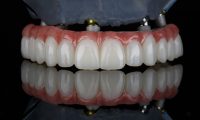

Real Dental Implant Results

Our patients have seen life-changing improvements in both appearance and oral function with a single dental implant. Whether from tooth loss, injury, or decay, we’ve helped individuals restore their smile and confidence with a natural, lasting solution.